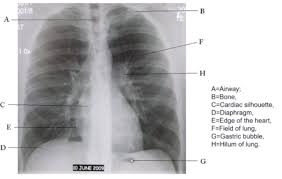

胸片,即胸部x光片,是医学上常用的一种检查手段,主要用于观察肺部、心脏、肋骨等胸部结构的异常情况。胸片曝光是指通过x射线对胸部进行照射,并将影像记录在胶片或数字探测器上的过程。这一过程的目的是为了辅助医生进行疾病诊断,而非满足个人好奇心或娱乐需求。

五、加强医学影像知识的普及与教育

为了提高公众对医学影像技术的认识和了解,减少因误解或无知而引发的担忧和恐慌,相关部门和机构应加强医学影像知识的普及与教育。通过举办讲座、制作宣传材料等方式,向公众普及医学影像技术的原理、应用及注意事项等方面的知识,帮助公众树立正确的医学影像观念。